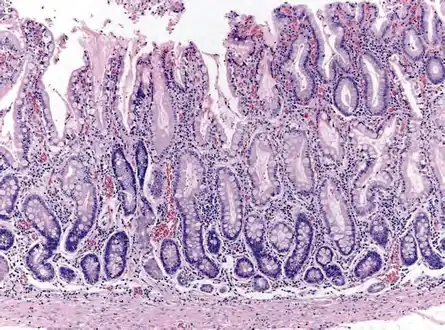

Atrophic gastritis is a process of chronic inflammation of the gastric mucosa of the stomach, leading to a loss of gastric glandular cells and their eventual replacement by intestinal and fibrous tissues. As a result, the stomach's secretion of essential substances such as hydrochloric acid, pepsin, and intrinsic factor is impaired, leading to digestive problems. The most common are vitamin B12 deficiency possibly leading to pernicious anemia; and malabsorption of iron, leading to iron deficiency anaemia.[2] It can be caused by persistent infection with Helicobacter pylori, or can be autoimmune in origin. Those with autoimmune atrophic gastritis (Type A gastritis) are statistically more likely to develop gastric carcinoma, Hashimoto's thyroiditis, and achlorhydria.

Autoimmune metaplastic atrophic gastritis (AMAG) is an inherited form of atrophic gastritis characterized by an immune response directed toward parietal cells and intrinsic factor.[6] The presence of serum antibodies to parietal cells and to intrinsic factor are characteristic findings. The autoimmune response subsequently leads to the destruction of parietal cells, which leads to profound Achlorhydria (and elevated gastrin levels). The inadequate production of intrinsic factor also leads to vitamin B12 malabsorption and pernicious anemia. AMAG is typically confined to the gastric body and fundus.